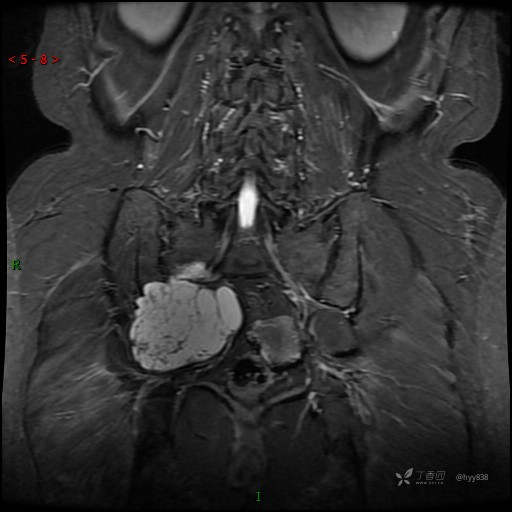

T2WI cor

腰痛按腰椎间盘诊治多年,影像检查却有意外发现,难度系数★★★☆---结果公布~

主诉:腰背痛5年余,加重伴右下肢麻木1年。

简要病史:患者5年前无明显诱因出现腰背部及右下肢疼痛,自觉为牵扯样酸胀痛,主要集中在右下肢后外侧,不伴下肢麻木,无明显间歇性跛行,曾间断在门诊行局部神经阻滞治疗、口服中药等,疼痛可部分缓解。近1年来,症状明显加重,出现右会阴部及右下肢麻木,久站久坐加重,平卧休息减轻。小便时阴部麻木不适,大便不畅,且自觉肛门坠胀。门诊以“腰椎间盘突出”收入我科。 患者发病以来,精神饮食可,睡眠可,二便欠佳,体力体重未见改变。

讨论:病变性质?鉴别诊断?